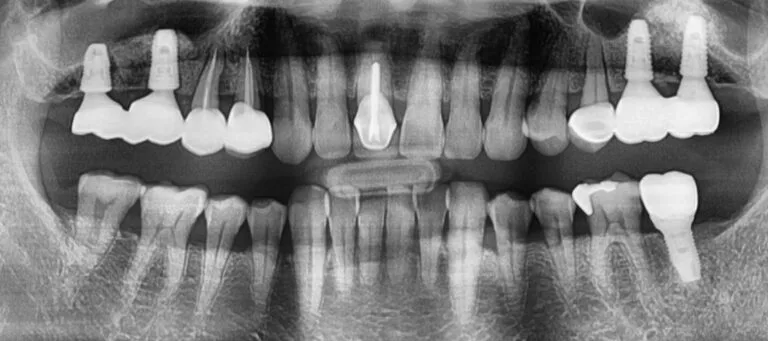

A 48-year-old gentleman sought relief at our Boston practice from persistent dental discomfort. Ten years prior, the loss of two upper left molars had understandably led him to favor his right side for chewing. This long-term compensatory habit resulted in significant strain and subsequent pain on his upper right side – a common scenario where […]